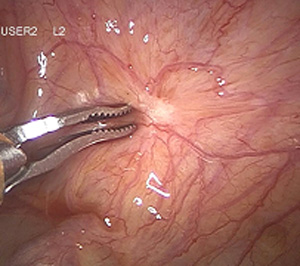

Myome, die sich in der Gebärmutterwand (intramural) oder auf der Außenseite (subserös) des Uterus befinden, können in aller Regel per Bauchspiegelung entfernt werden, dabei wird ein sogenanntes Laparoskop durch den Bauchnabel geführt. Verbunden mit einem Kamerasystem ermöglicht es dem Operateur im Bauch "sehen" zu können. Mit zwei bis drei zusätzlichen Instrumenten können die Myome mittels minimal-invasiver Operationstechnik aus der Gebärmutter "herausgeschält" und entfernt werden. Die Gebärmutter wird dann wieder vernäht. Vor einer eventuell geplanten Schwangerschaft wird empfohlen, einen Zeitraum von drei bis sechs Monaten abzuwarten. Die Technik der Laparoskopie ermöglicht es, die mit einem Bauchschnitt verbundenen Schmerzen zu vermeiden - dennoch kann es unter Umständen sinnvoll sein, sehr große oder ungünstig gelegene Myome, durch einen Bauchschnitt zu entfernen